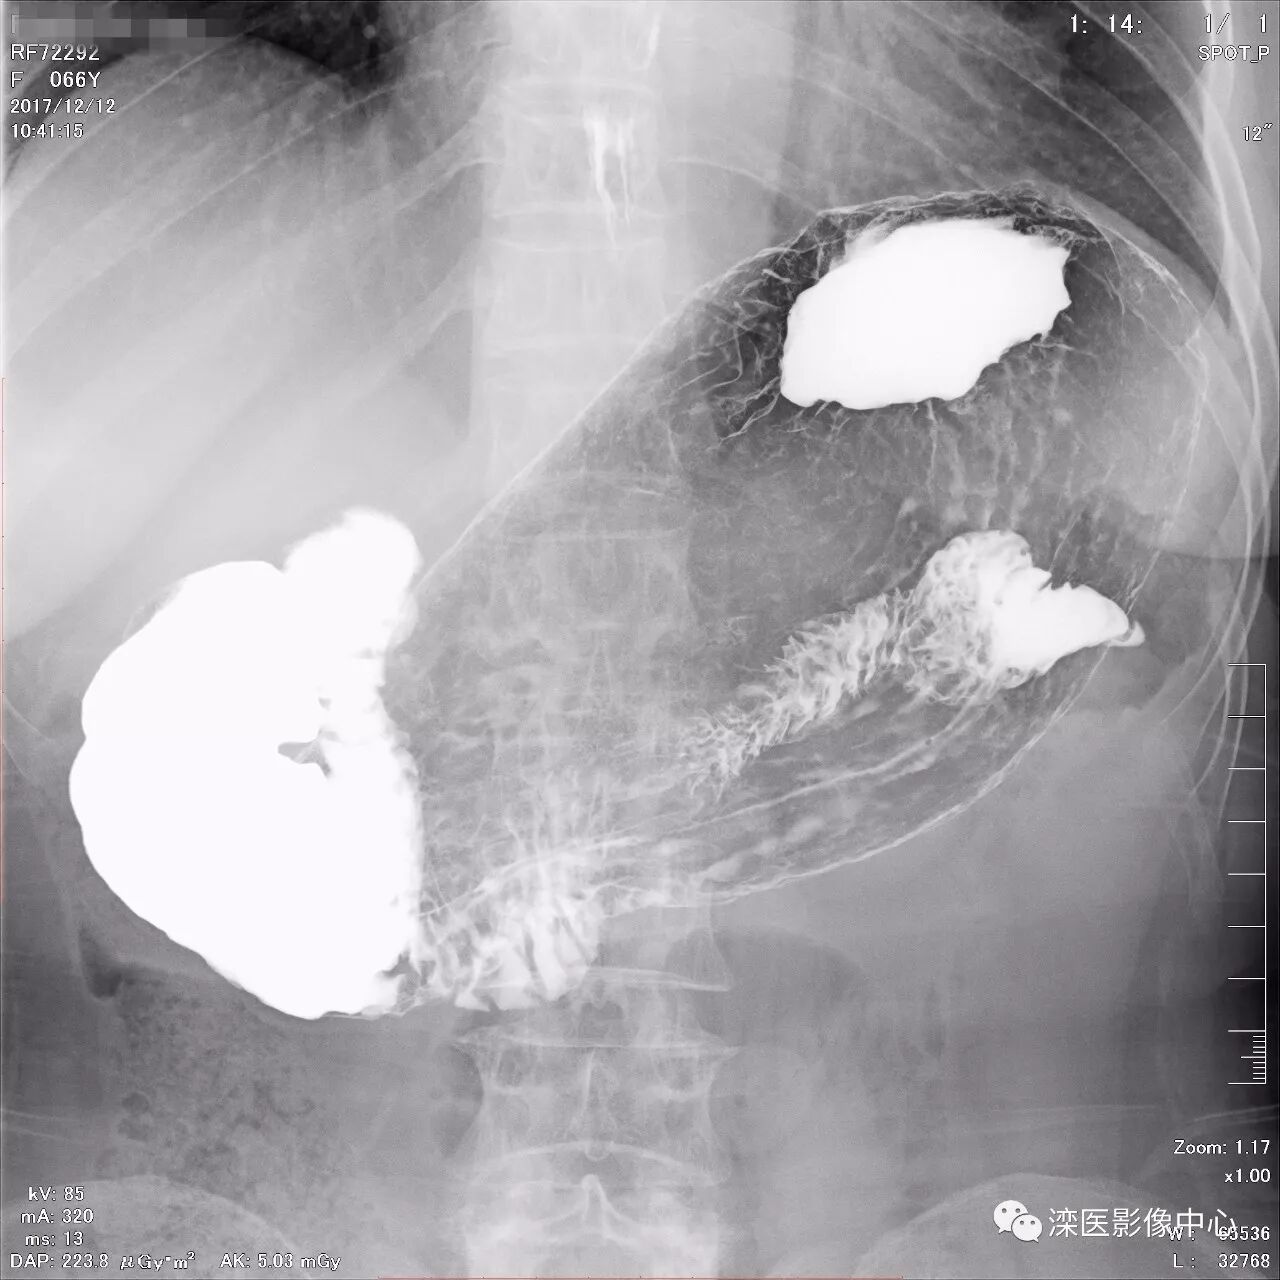

(以上图像是患者立位+卧位,通过变换体位,多角度显示了贲门胃底、胃体、胃大弯、胃小弯、胃窦、幽门及十二指肠球部、降部、水平部、升部的粘膜像和充盈像。本例患者女性,66岁,此次检查可以清晰显示胃小区结构,检查中发现患有慢性胃炎、胃下垂、十二指肠降部憩室)